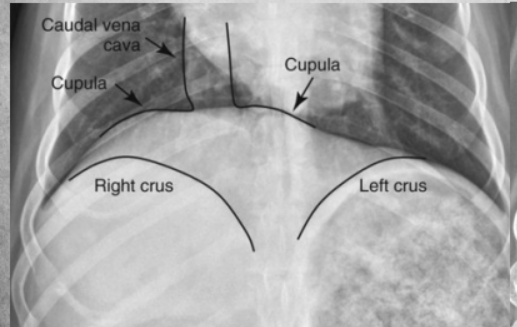

In right lateral:

the diaphragmatic crura are parallel (in left, they form a V)

in right lateral, the caudal vena cava merges with the cranially positioned crus and with the caudal when its left lateral

left lung is seen better in right lateral

heart more egg-shaped in right lateral, rounder in left.

In left lateral: blood vessels of cranial lobes are easier to differentiate.

thoracic lymph nodes may be seen in right lateral but rarely ever in left lateral.